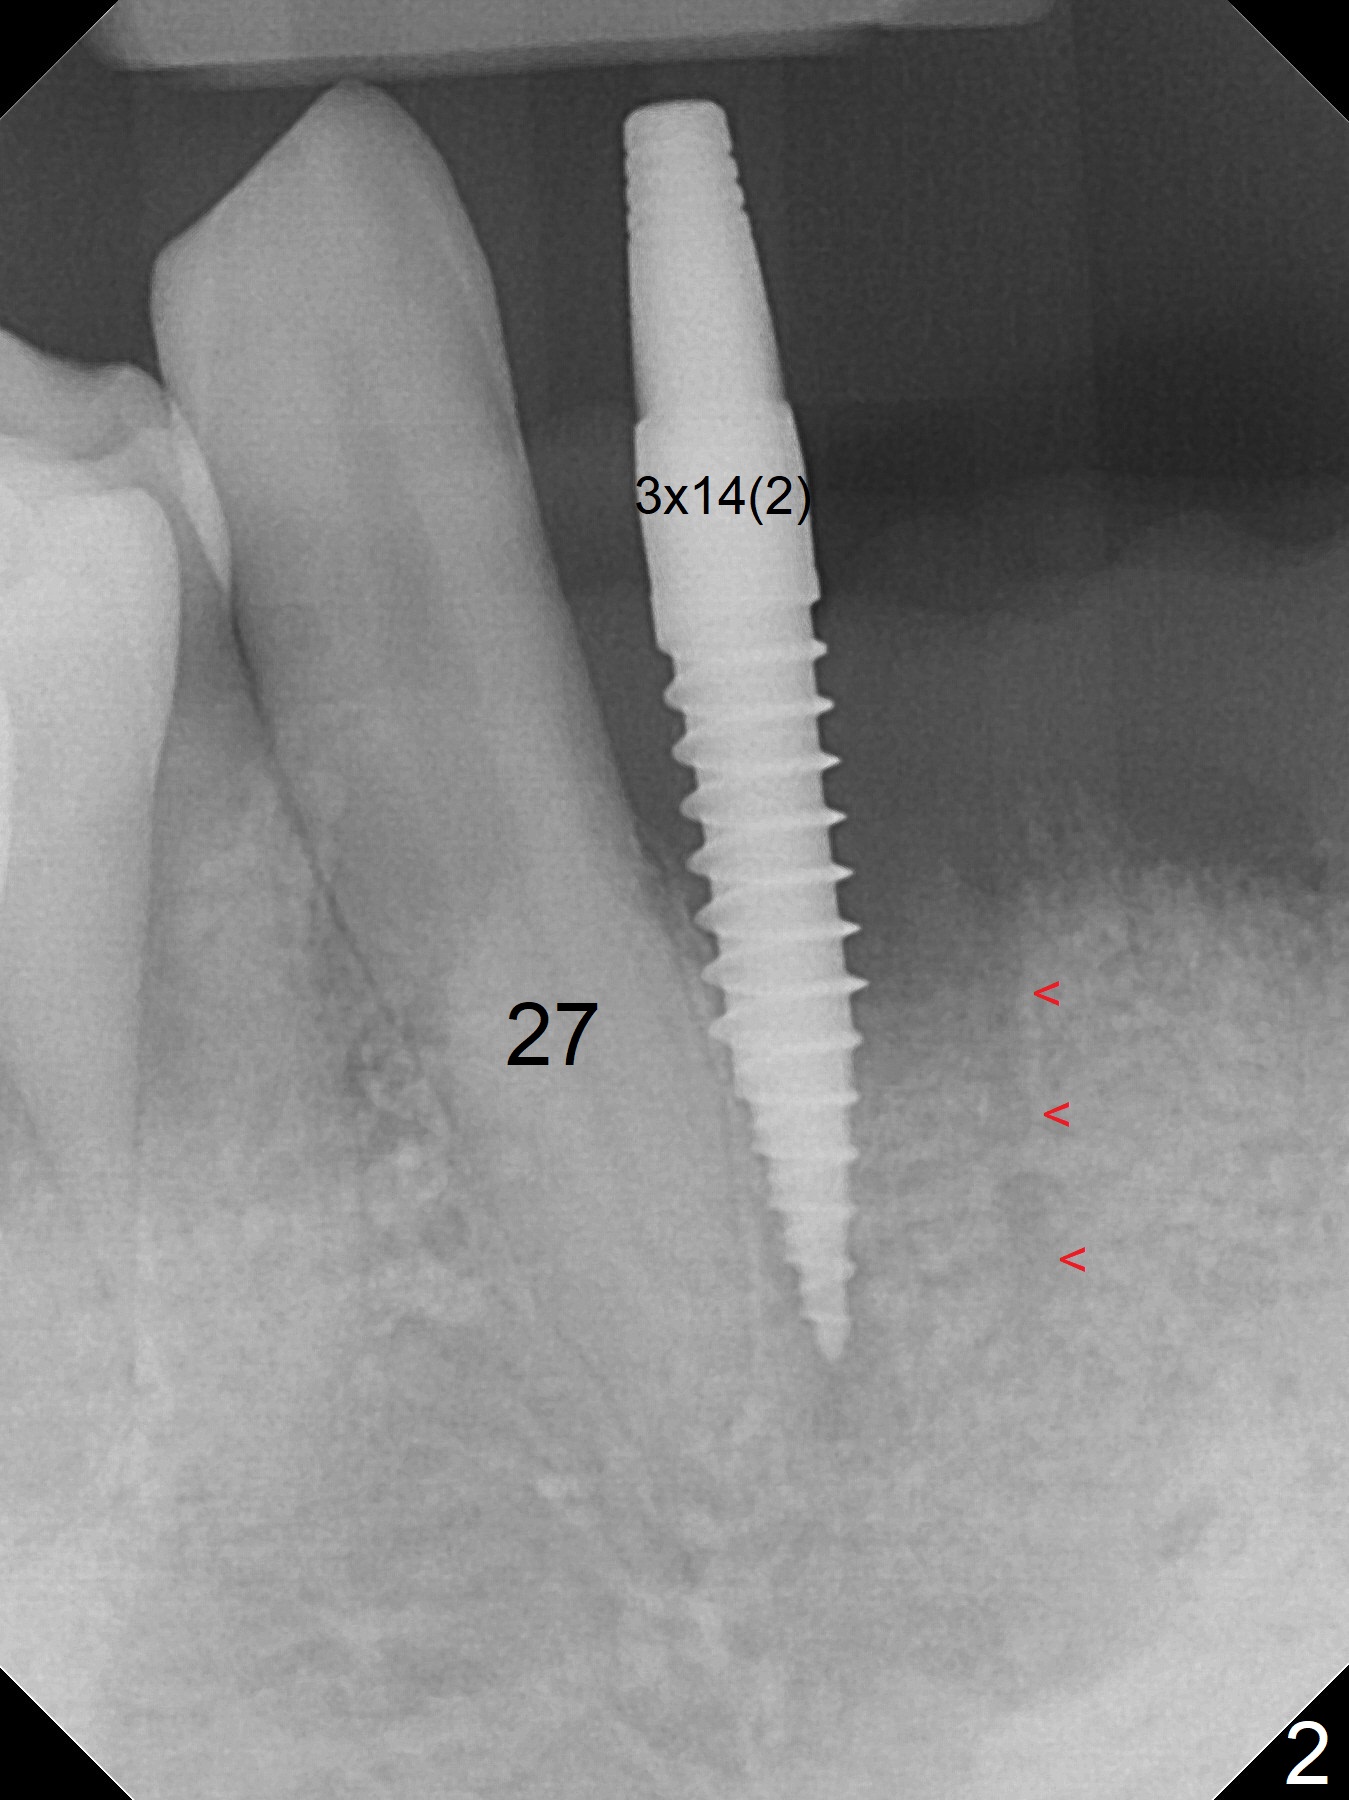

After extraction of 4 of the lower incisors, there are basically 2 sockets (#23/24 and 25/26), separated by the apparently midline bone (Fig.1 red line).  In spite of using Lindamann bur to move the 25/26 osteotomy mesially, a 3x14(2) mm dummy implant remains close to the tooth #27 (Fig.2).  The terminal branch of the Incisive Canal (<) is located between the lateral and central incisors.  A de novo osteotomy (Fig.3 (1.5 mm drill)) is made mesial to the original one (O).  While the 3x14(2) mm dummy implant is incompletely placed at #25/26, a 3x14(4) mm 1-piece one is placed at #23/24 (Fig.4).  Finally the same implant is placed at #25/26 with placement of mineralized cortical/cancellous bone (Fig.5 *).  When the large sockets are sutured, the supraerupted teeth #7-9 touch the lower gingiva (Fig.6).  The incisal edge is reduced for clearance (Fig.7).  Periodontal dressing is less likely to be dislodged with the incisal edge reduction (Fig.8,9).  A provisional FPD is fabricated 1 week postop.  Hard (Fig.10) and soft (Fig.11,12) tissues heal 5.5 months postop.  The patient returns for crown cementation 3 months post impression (9 months postop, Fig.13,14).